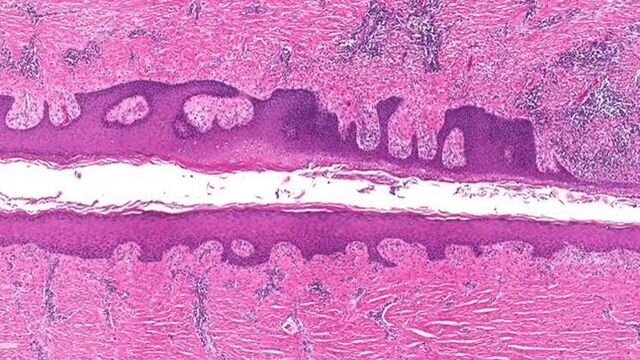

Гнойный гидраденит (ГГ) представляет собой хроническое воспалительное фолликулярное заболевание, при котором под кожей образуются болезненные уплотнения. Уплотнения обычно образуются в местах соприкосновения кожи, таких как подмышки, пах и под грудью. Тяжесть ГГ может варьироваться от случайных абсцессов, заполненных жидкостью, до широко распространенных веретеноподобных рубцов, хронической боли и роста инфекции.

Ген SOX9 выполняет две функции в организме: поддерживает структуру волосяного фолликула и определяет стволовые клетки, чтобы стать или дифференцироваться в клетки, выстилающие волосяной фолликул. SOX9 также запускает активацию трех других генов: MMP1, MMP2 и IL-8, которые связаны с образованием базально-клеточной карциномы, меланомы и воспаления.

Другой предполагаемый ген, KLF5, способствует образованию кератиноцитов — преобладающего типа клеток в эпидермисе — и секреции ферментов, поедающих омертвевшие клетки кожи. Если его не остановить, организм вырабатывает так много кератина, что эпидермис утолщается, а волосяные фолликулы могут блокироваться.

Вариации этого гена могут объяснить развитие характерных кист и бугорков, наблюдаемых у пациентов с ГГ. В то время как KLF5 функционирует для контроля уровня эпидермальных стволовых клеток, SOX9 делает то же самое для стволовых клеток волосяного фолликула.

Если этот тщательный баланс между паттернами экспрессии нарушается генетическими факторами, это может объяснить, почему в организме образуются хронические раны, такие как воспалительные язвы, а также кисты и эпителизированные каналы.